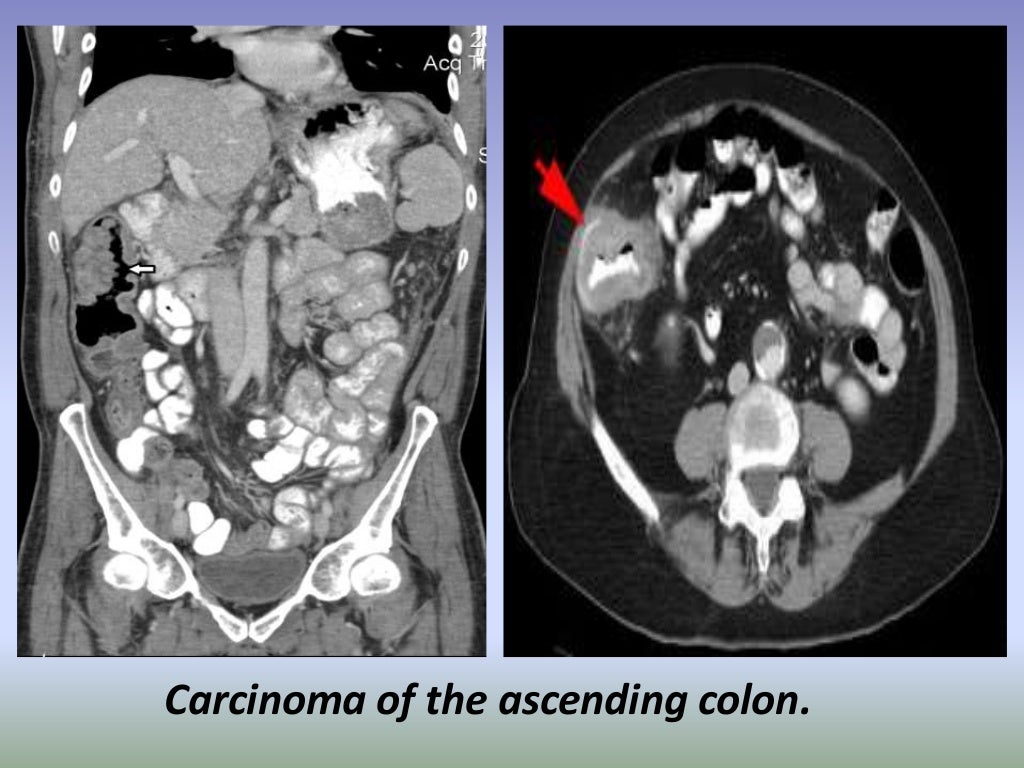

Presentation1.pptx, radiological imaging of large bowel diseases Large Bowel Disease Diagnosis inflammatory bowel disease (ibd) encompasses two conditions: inflammatory bowel disease is a term that refers to crohn’s disease and ulcerative colitis, two inflammatory conditions that affect as. Crohn’s disease and ulcerative colitis. inflammatory bowel disease (ibd) refers to diseases that cause chronic inflammation in your gastrointestinal (gi). chronic diarrhea and belly pain could be caused by. Large Bowel Disease Diagnosis.